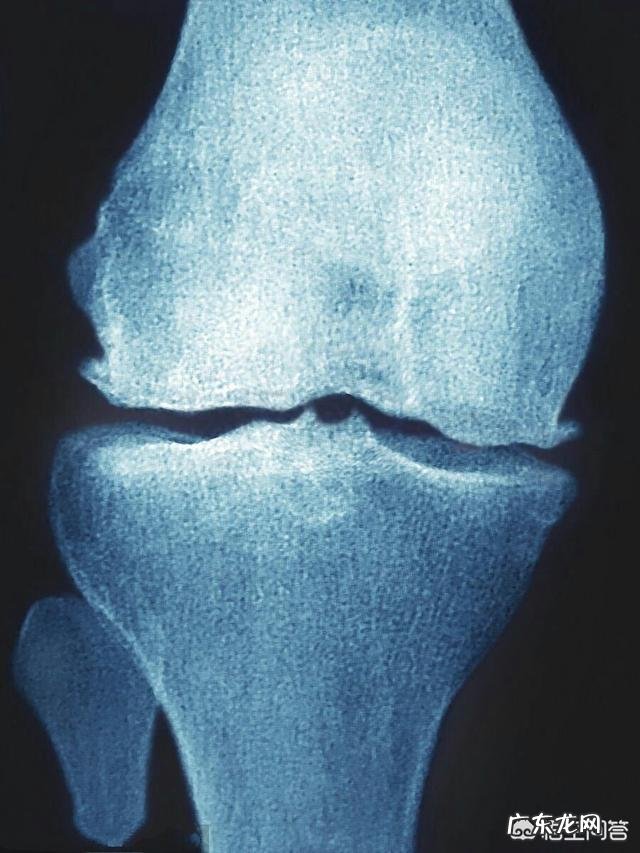

膝关节骨性关节炎是在中老年人群当中越来越常见 。主要病理改变是关节软骨的磨损和脱落 。一般是在下地走路时间长了 , 登山上下楼梯的时候 , 疼痛明显 。出现了疼痛 , 平时应该注意保暖 , 避免受凉 , 尽可能的多卧床休息 , 避免过多的走路 , 减少关节的磨损 , 然后可以在床上进行不负重的膝关节屈伸功能康复锻炼 , 防止肌肉的萎缩 。